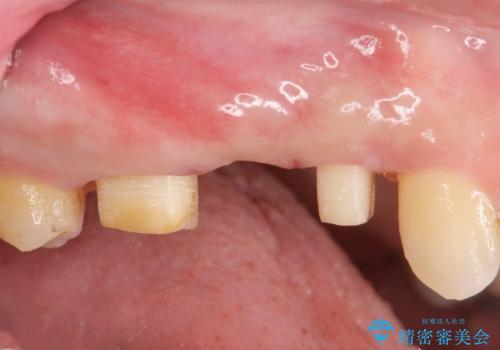

検査をしたところ、右上小臼歯に破折が見られ保存が難しい状況です。

抜歯を行い、咬合機能の回復を行いますが、咬合関係や非常に強い噛み合わせの問題をふまえ、咬合面をメタルにしたメタルボンドブリッジで治療を行うこととしました。

また噛み合わせが深くブリッジの強度が十分に確保できないことから、抜歯時に歯周外科を行うことで十分に安定したクラウン装着をできるような処置を行っています。

術前・術後でブリッジ治療をした部分の歯肉ラインを整えたことで安定したブリッジを製作することができました。